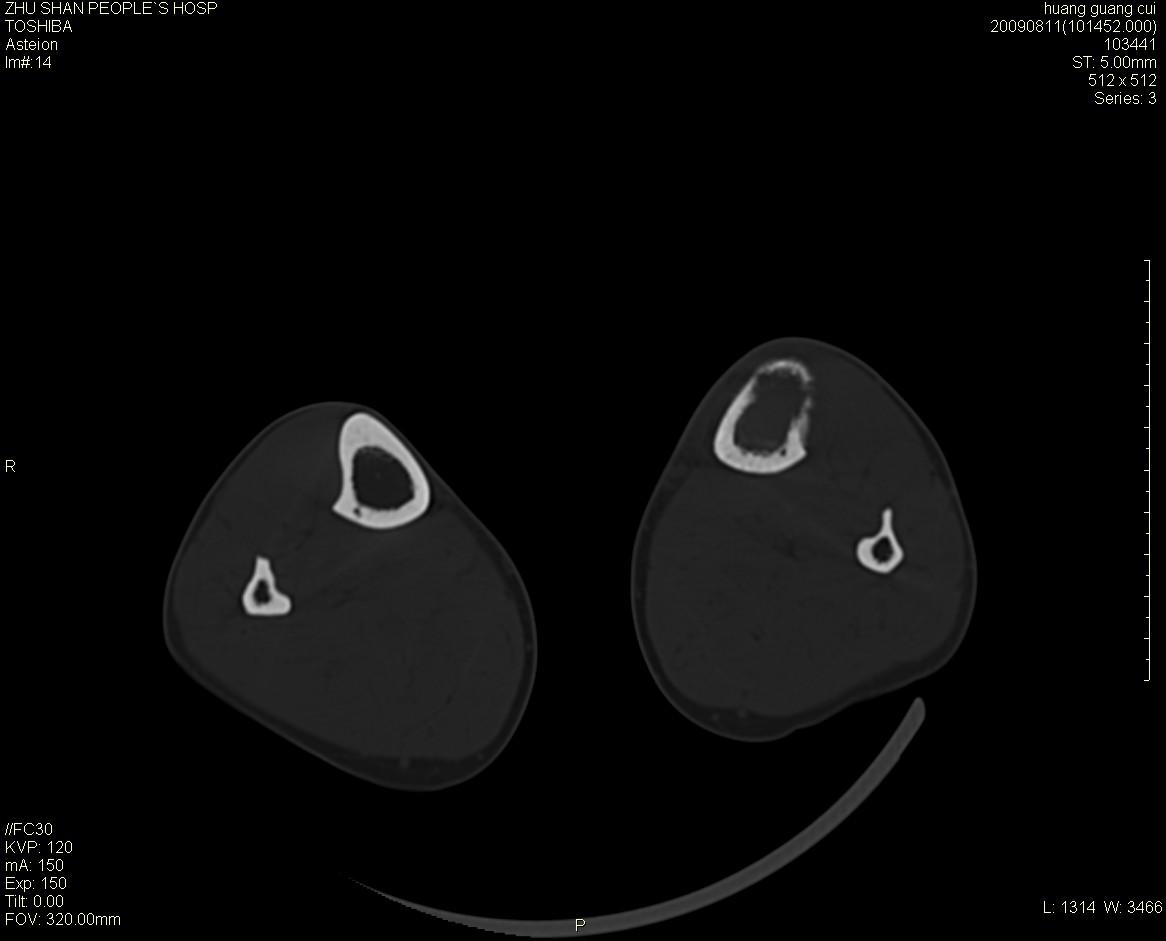

左侧胫骨中段骨皮质溶骨性破坏,髓腔内外见软组织肿块,无明显钙化及成骨,定位相显示病变周围“筛孔样”改变,定性恶性无疑,原发或转移均有可能,倾向于骨纤维肉瘤可能性大,转移瘤不排除。膝关节以下骨转移很少,且要有原发灶支持,尤文氏肉瘤年龄太大不支持。